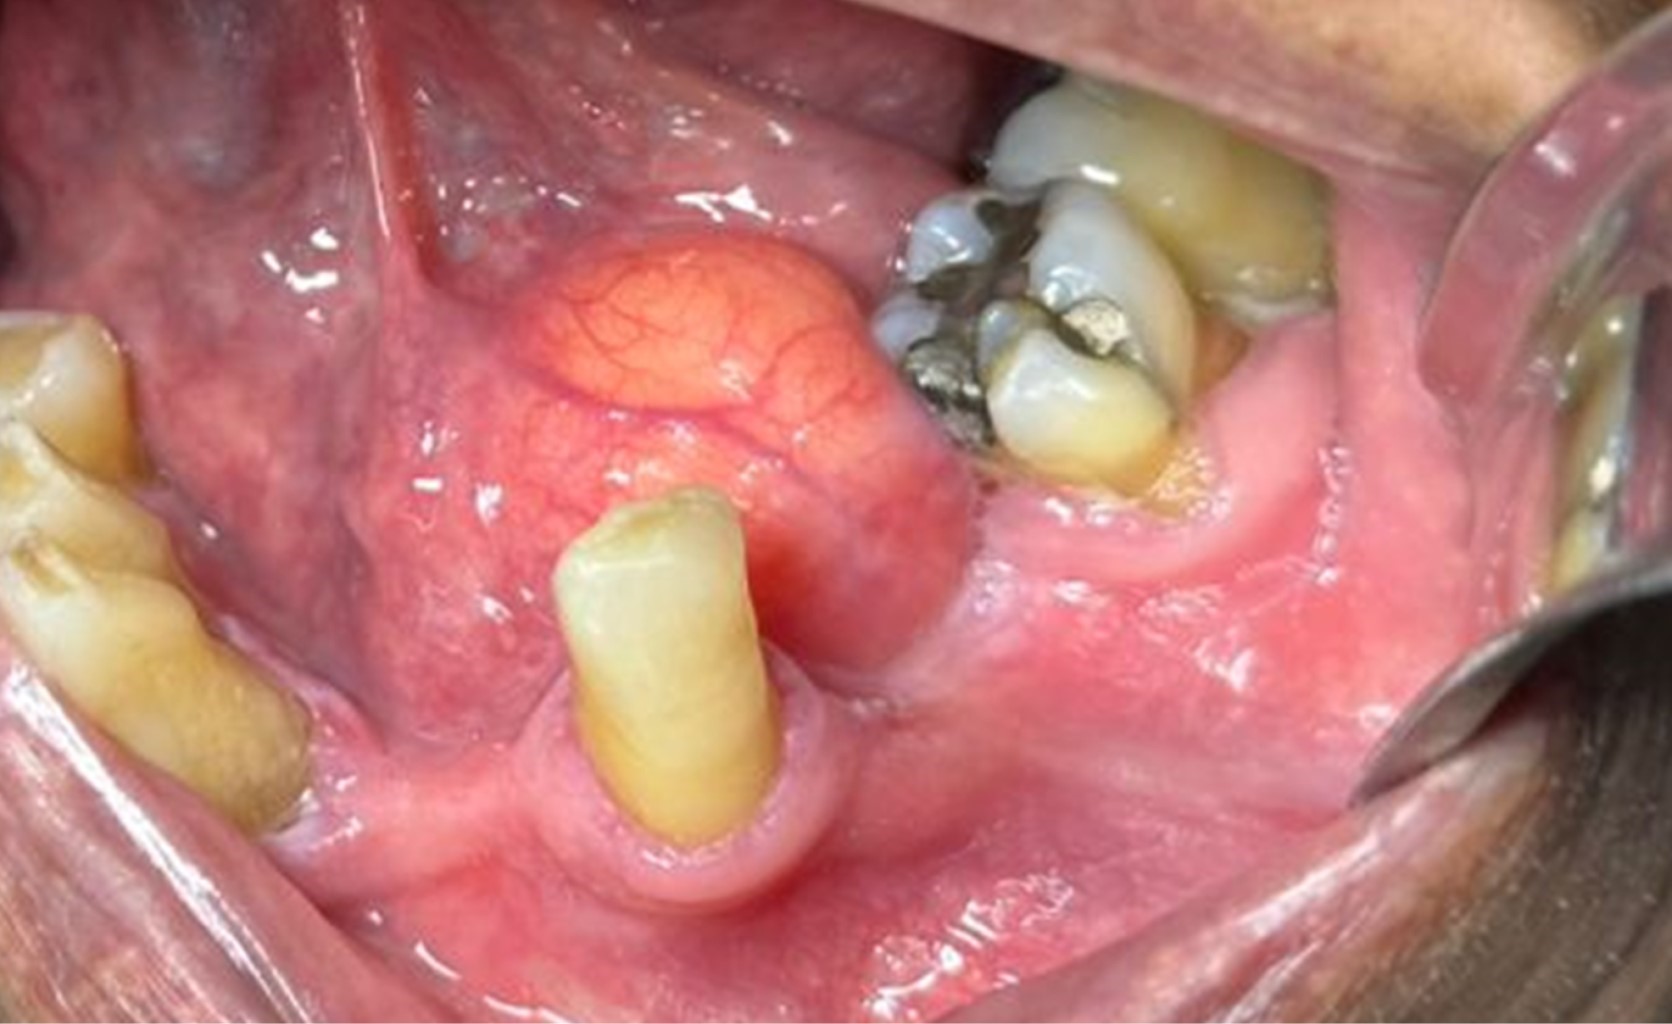

En el examen clínico extraoral no se evidenciaron aumentos de volumen ni asimetrías faciales. Durante examen clínico intraoral se evidenció aumento de volumen de color amarillento en piso de boca, con predominio del lado izquierdo, circunscrito, depresible a la palpación, con un tamaño aproximado de 3 × 2 cm de diámetro (Figura 1).

Basado en los hallazgos clínicos, un diagnóstico diferencial clínico de Lipoma fue dado, donde posteriormente se decidió la realización de toma de biopsia excisional de lesión bajo anestesia local (Figura 2).

Figura 1